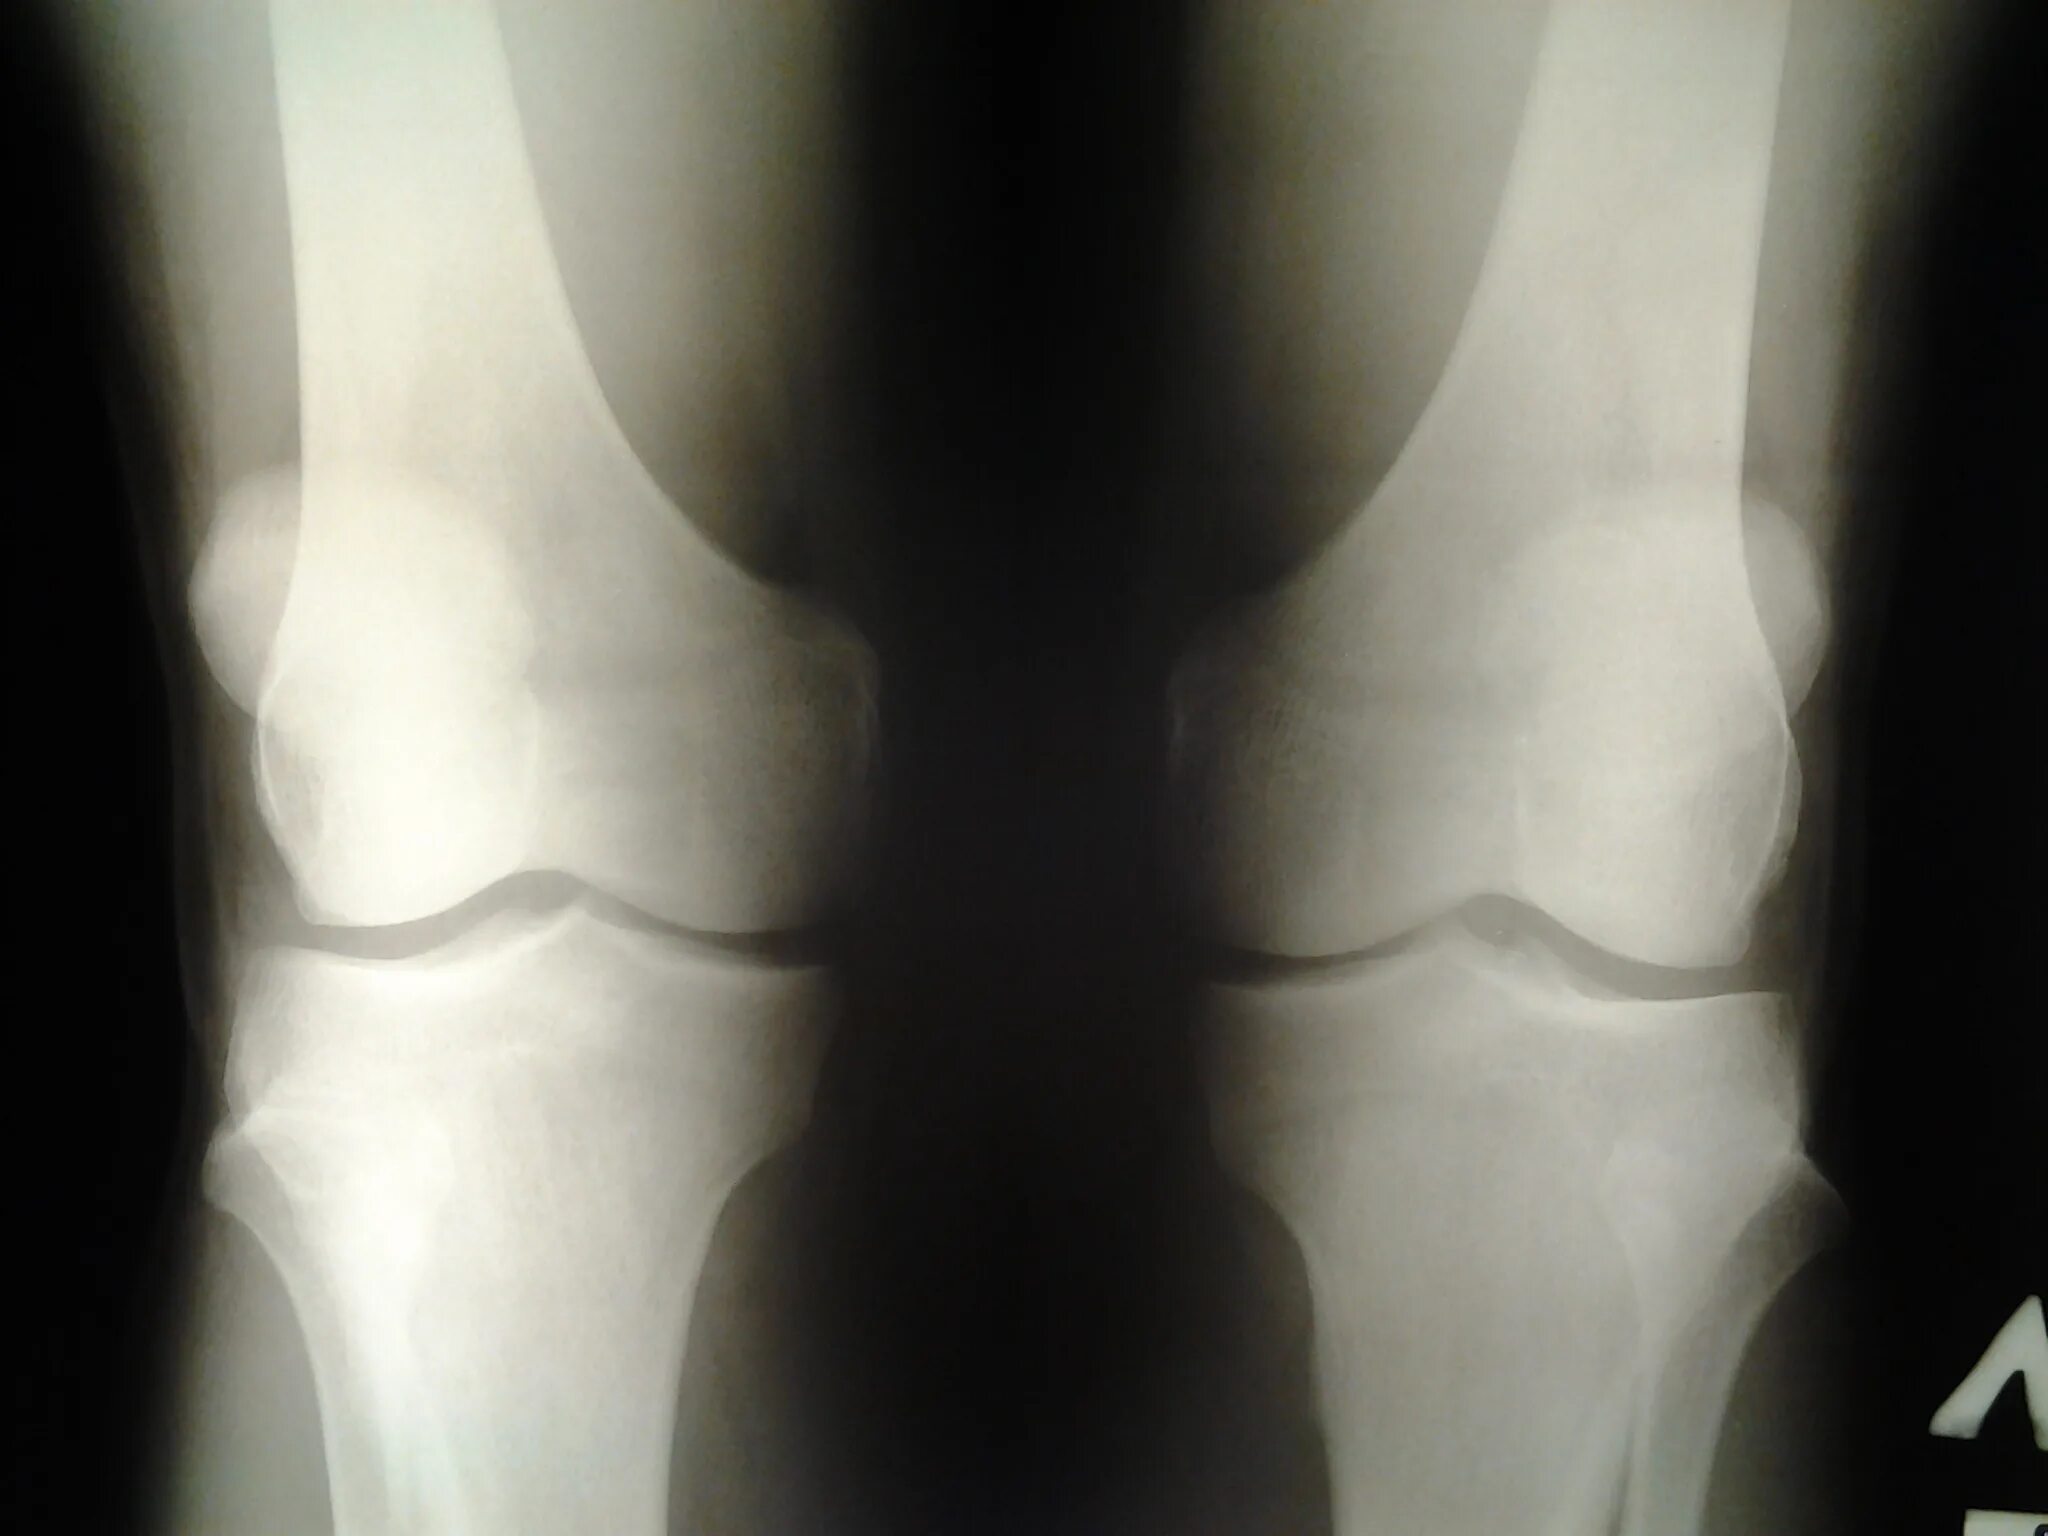

Лигаментоз коленного сустава. лигаментоз связок коленного сустава. лигаментоз тазобедренного сустава. лигаментоз крестообразных связок рентген.

Лигаментоз коленного сустава рентген. лигаментоз надколенника рентген. рентген коленного сустава пкс. повреждение связок коленного сустава рентген.

Лигаментоз коленного сустава рентген. тендиноз коленного сустава рентген. пороз коленного сустава рентген. лигаментоз коленного сустава рентгенологическая картина.

Остеомиелит коленного сустава рентген. лигаментоз коленного сустава. остеопороз коленного сустава рентген. пятнистый остеопороз коленного сустава.